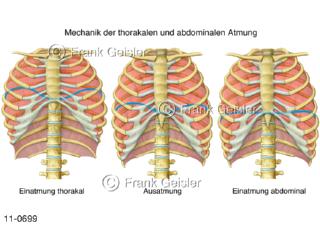

11-0699 Physiologie Atmung, Ventilation, Atmung thorakal abdominal, Einatmung und Ausatmung